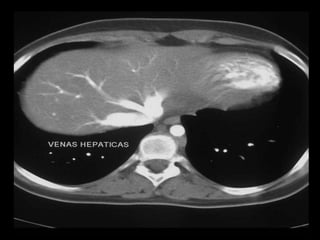

VASCULARIZACION HEPATICA

TRES SISTEMAS

VASCULARES:

• ARTERIA

HEPATICA

• VENAS

SUPRAHEPATICAS

• VENA PORTA